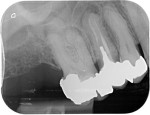

Root canal treatment can be a difficult procedure for the dentist to perform to the internal complexity of the canal system.

On the second appointment we do the same procedure with local anaesthetic and disinfect and prepare the canals, once we are happy with our preparation the canals are sealed with rubber points and a sealant into each canal. Radiographs may be taken to check our progress before sealing. A temporary restoration may be placed depending if the tooth requires further treatment.

Unfortunately root canal treated teeth are more prone to fracturing than unrestored teeth, a crown or inlay may be required although the dentist will discuss this with you prior to treatment commencing.

A follow up x-rays is normally taken a year after completion to ensure any areas of infection are healing.